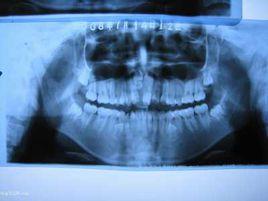

多生齒的數目不等、形態特殊、位置不定、生長速度不一。

阻生齒是恆牙在發育過程中發生偏離了正常位置的牙齒。屬於32顆範圍內的牙齒。

多生齒是超出32顆範圍的牙齒,如果多生齒長在牙齦位置也會產生阻生齒一樣的影響。